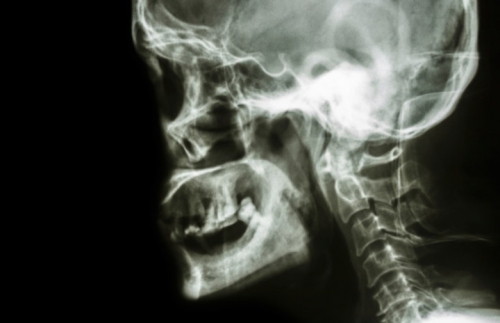

Zbog stalnog krvarenja iz nosa, mladi se Saudijac obratio liječniku. Nalazi rendgenskih snimki otkrili su da mu u nosu raste zub dug oko 1,3 centimetra, objavio je časopis American Journal of Case Reports. Riječ je o takozvanom intranazalnom prekobrojnom zubu koji mu je grebao unutrašnjost nosa i tako uzrokovao krvarenja. Vrlo rijetki, prekobrojni zubi pojavljuju se blizu sjekutića i povremeno rastu prema gore. Nosni zub uspješno mu je uklonjen uz primjenu anestetika.